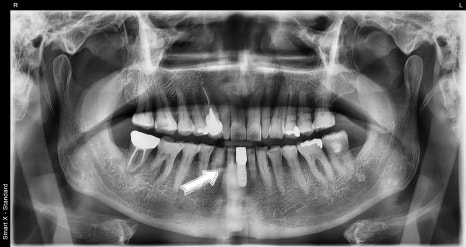

수술 후 엑스레이임플란트가 안정적으로 자리 잡았고,

주변 뼈 상태도 양호하게 유지되고 있습니다.

환자분은 수술 직후 통증이 거의 없었으며,

치료 후에는 음식 섭취와 발음에 대한 불편함 없이

일상생활에 복귀하셨습니다.